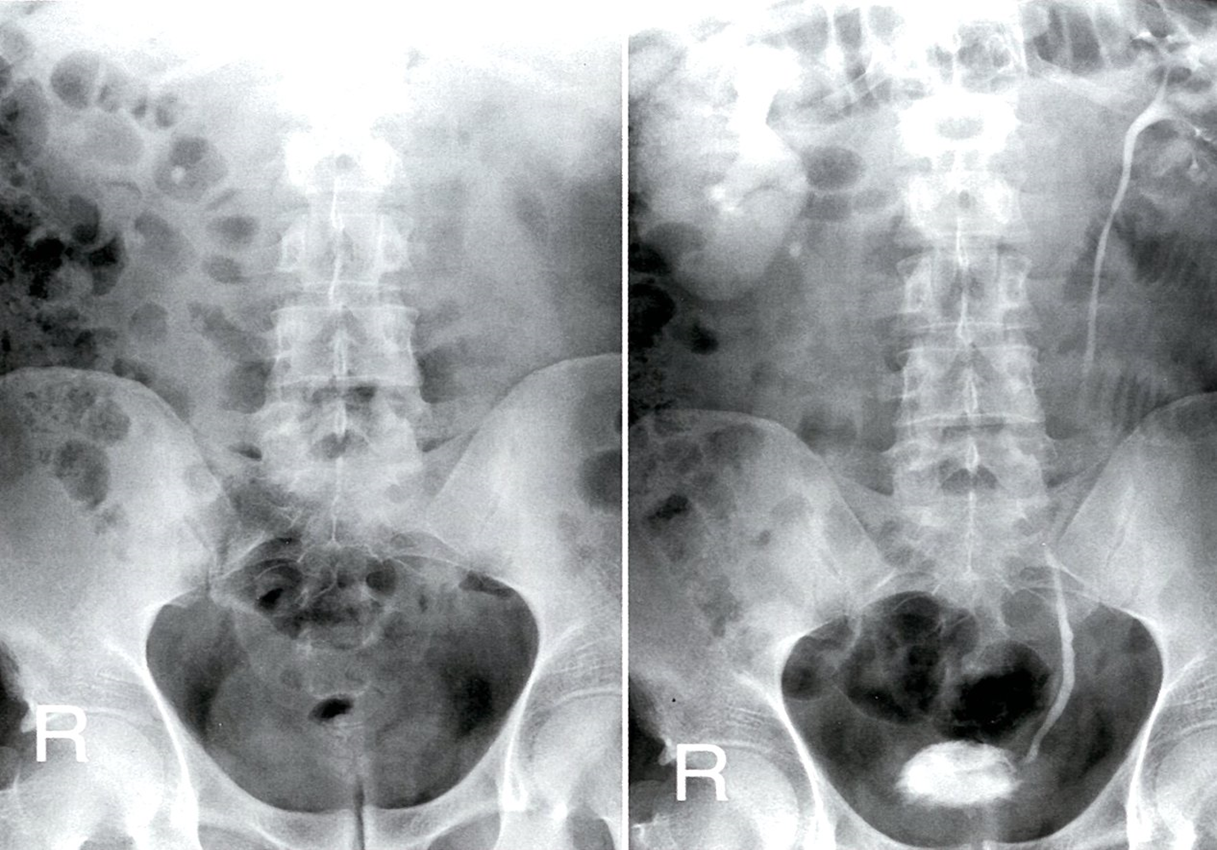

Excretory urography (AP view; left: pre-contrast; right: 2.5 hours post-contrast)

A calcification medial to the lower pole of the right kidney on the pre-contrast radiograph is shown post-contrast to be an obstructing proximal ureteral calculus. The right kidney is enlarged, with persistent enhancement. There is pelvicaliectasis and poor contrast-filling of the right ureter. The left renal collecting system is normal.